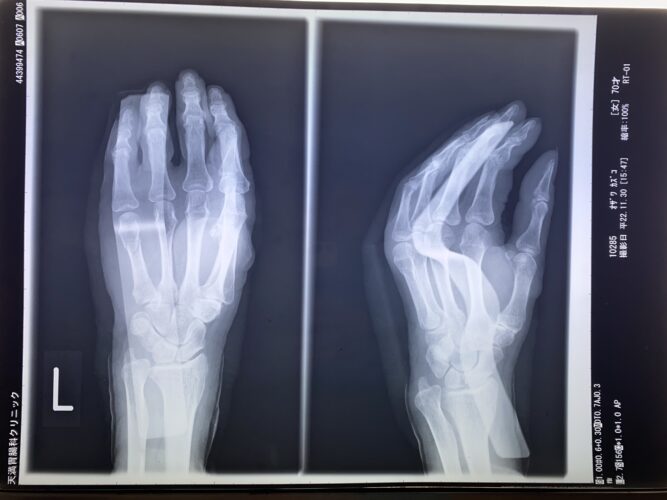

第16回整骨研究会「賜恩」研修会開催

さわやか千葉県民プラザ(指骨骨折)

第18回整骨研究会「賜恩」研修会開催